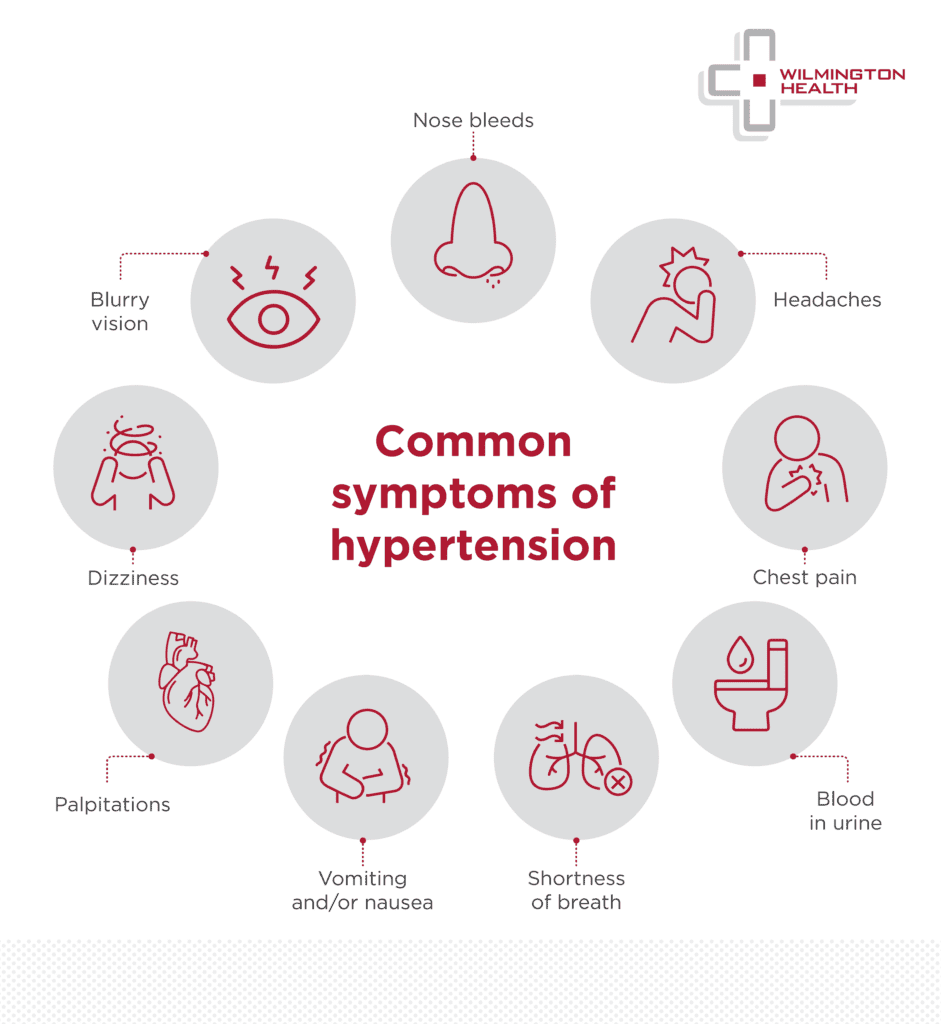

Understanding Hypertension Wilmington Health

https://www.wilmingtonhealth.com/wp-content/uploads/2023/04/23-WILMHEAL-0388-Website_Graphics_and_Copy-Symptoms-0130-P1-01-941x1024.png

Hypertension Symptoms Causes Types Complications Prevention